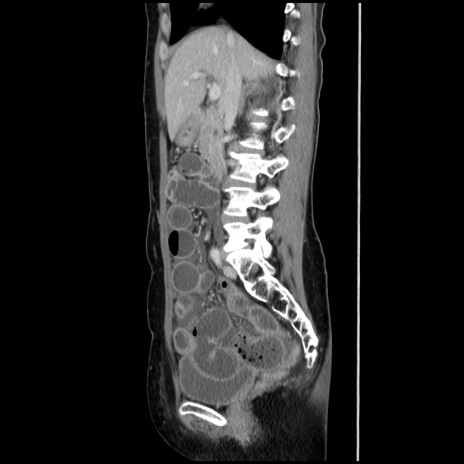

症例32(矢状断像)

【症例】40歳代 女性

【主訴】上腹部痛、嘔気・嘔吐

【現病歴】約9時間前頃から急に上腹部痛、嘔気、嘔吐が出現。改善しないため救急要請。

【既往歴】子宮頚癌(広汎子宮全摘術、放射線療法)、腸閉塞

【身体所見】腹部:平坦、軟、腸雑音亢進、上腹部を中心に腹部全体に圧痛あり。

【データ】WBC 8400、CRP 0.03